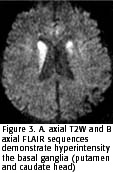

The MRI was performed at the presentation and revealed hyperintensity of the basal ganglia on T2W, FLAIR and DWI sequences. The T1W sequence showed a slight hypointensity of the basal ganglia and no contrast enhancement (Figure 3 and 4). The ADC was 0,44 x 10-3 mm2/s in the putamen and 0,41 x 10-3 mm2/s in the caudate head, confirming restriction of water diffusion (5). Basic biochemical and serological exams were performed and were negative.

Moreover, both patients showed signal changes on T2W and FLAIR in the putamen and caudate nuclei early in the course of the disease (2 to 4 months after first symptoms). In addition, the DWI sequence demonstrated restriction of the water motion in the striatum. The striatal hyperintensity could be seen early in the evolution of sCJD and supported the clinical diagnosis (2, 5-7, 9). The DWI is the most specific for the diagnosis of sCJD (2). Many diseases could manifest with basal ganglia hyperintensity on T2W, DWI and FLAIR images (ischemic, edematous, metabolic and toxic lesions, inborn errors of metabolism, Leigh's disease and mitochondrial encephalomyopathies in general), but these findings are transitory and observed in the acute phases of these diseases only (9). The persistence of the DWI hyperintensity images associated with typical clinical signs greatly suggests sCJD (2). Although, there are few reports about late phase of sCJD and we do not know for how long the restriction of water motion could be noted on the DWI.